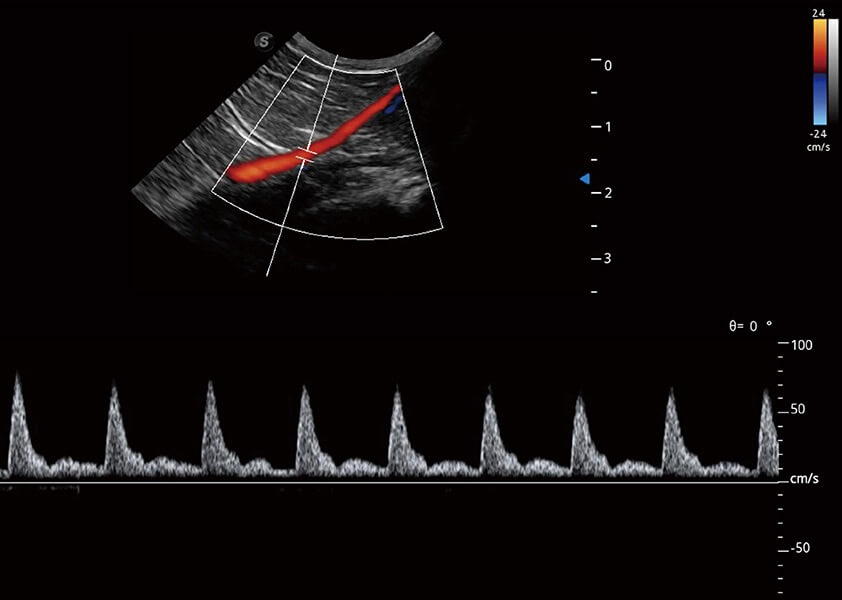

ProPet 60 作為一款高端臺(tái)式動(dòng)物超聲設(shè)備,為動(dòng)物醫(yī)生的日常診斷提供了一系列貼合動(dòng)物臨床需求、解決臨床實(shí)際問題的高級成像功能。憑借全系列高清探頭,滿足醫(yī)生對腹部、心臟、生殖、淺表、肌骨等成像的所有需求,切實(shí)幫助您提升檢查效率,提高診斷信心。